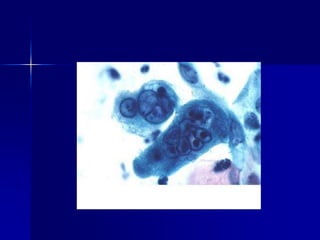

Marcadores tumorales en la identificación de neoplasias

indiferenciadas. Metástasis de melanoma en colon.

Marcadores tumorales enla identificación de neoplasias indiferenciadas. Metástasis de melanoma en colon.